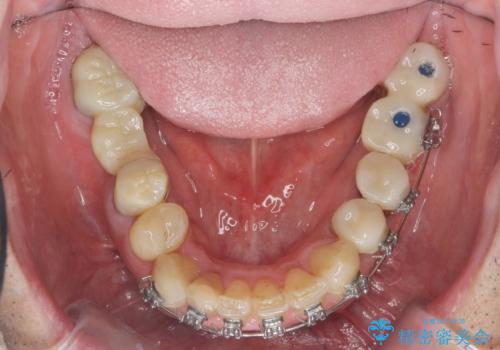

- 「少しずつ色々な箇所が悪くなり、歯医者に通い続けている。全ての歯を長持ちするような状態にできるような治療を受けたい。」、と全顎・総合的な治療を希望され来院されました。

根管治療・矯正治療・歯周外科・セラミック補綴を含む様々な治療オプションを駆使し、長期間良好な状態に保てるような治療計画を立案します。

矯正治療を絡めた総合的な治療をお行なったことで、理想的な咬合関係を確立し安定した噛み合わせで仕上げることができました。

また歯周外科を行うことで歯ぐきの腫れを改善し、清掃性を高めています。